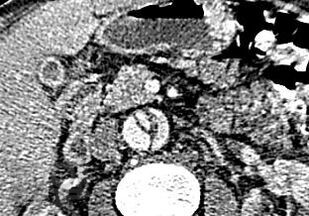

Расслоение аорты: эпидемиология, этиопатогенез, диагностика

Пособие содержит материал, отражающий представления об эпидемиологии, этиопатогенезе расслоения аорты. Подробно изложены существующие классификации расслоения, а также современные методы клинико-лабораторной и инструментальной диагностики при данной патологии.